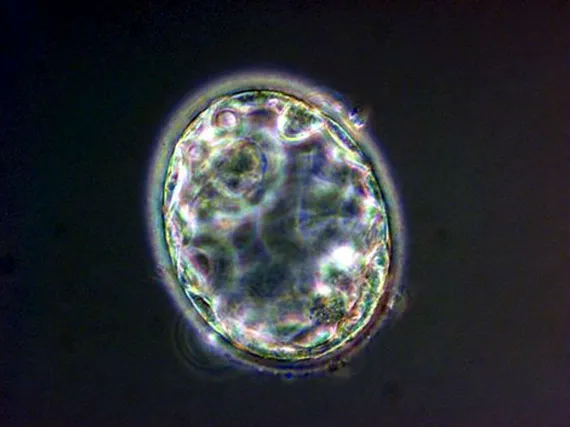

Kuvassa viisi päivää vanha alkio.

KUVA: EPA / All Over Press